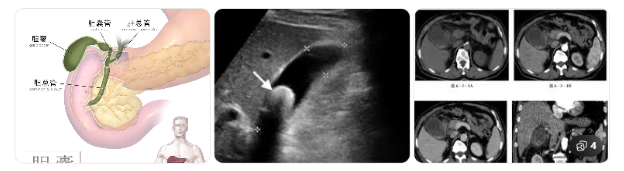

胆囊是位于肝脏下方的一个“小囊袋”,主要负责储存胆汁,帮助消化脂肪。

急性胆囊炎通常发生在:胆结石堵住胆囊出口、胆汁排不出去、胆囊压力升高并发生感染。就像水管被石头卡住,越堵越胀,最终引发剧烈疼痛和炎症。